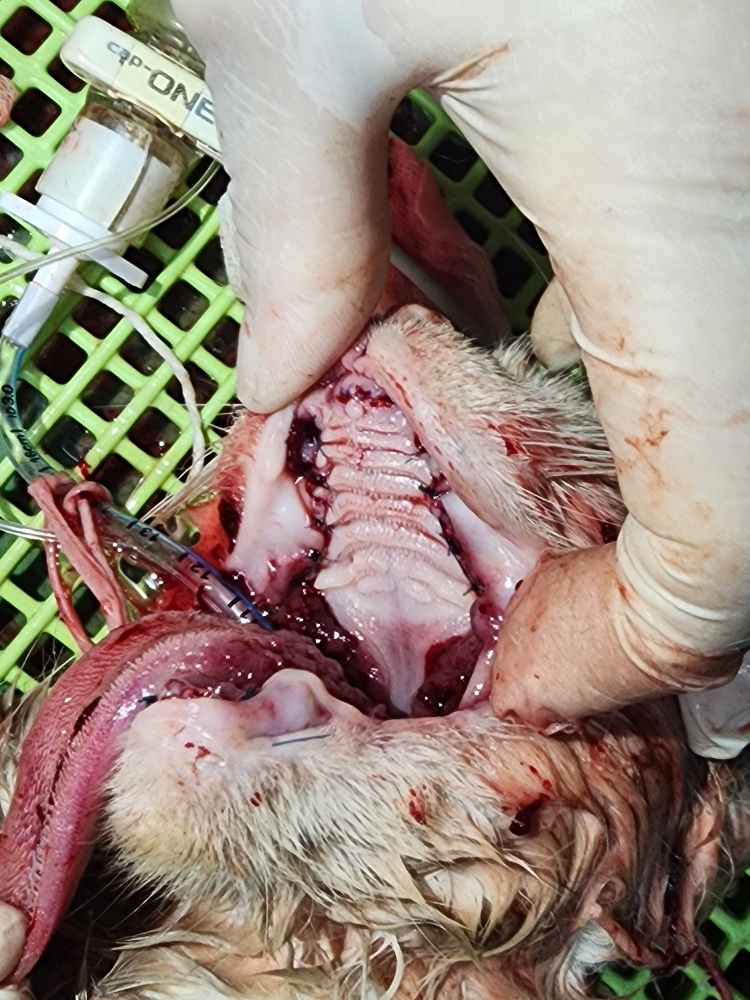

같이 구조한 소리아빠의 구조치료후 및 구조전 사진입니다.

| 대상묘신청당시상태 | 소리는 구내염이 심하여 침을 질질 흘렸고 고름도 흘리고, 눈에 염증도 있었습니다. 심한 탈수 상태로 건강이 급속히 악화되어갔습니다. 몇개월 동안 소리의 면역력 강화를 위해 꾸준히 영양제 및 항생제 급여로 케어해주었으나 상태가 점점 더 심해져만 갔고 잘먹지를 못했습니다. 소리는 중성화도 미실시된 상태였습니다. 새끼를 여러마리를 낳았으나 건강상태가 좋지 않아 제대로 수유를 하지 못해 한마리만 겨우 살아남아 수유중이었으나 어미모인 소리 상태가 좋지 않아 새끼와 같이 구조하였습니다. 같이 입원시켰으나 수유를 하지 않아 새끼는 인공수유 및 별도 케어중입니다. |

| 치료과정 | 올해 3월부터 하천 다리 밑에서 생활하던 치즈 가족인데 환경이 열악하여 돌보기 시작하여 조금씩 건강이 좋아지다 일주정도 사라졌다 다시나타났을때 상태가 좋지않아 이틀간 지켜보다 점점악화되어 가서 일가족을 8/14 저녁에 구조하여 15일 병원개원전 도착하여 1번으로 입원시켰습니다. 초기진료시 심한 구내염과 심한 탈수로 우선 수액부터 공급하시고 저녁쯤 전발치 수술을 하였어요. 중성화가 되어 있지 않아 수술을 같이 진행하였습니다. 한달전쯤 출산하여 새끼가 여러마리였으나 아빠냥, 엄마냥 모두가 심한 구내염과 치주염 그리고 탈수로 제대로 케어하지 못해 한아이만 살아있어 같이 구조했는데 소리 수술후 같은 케이지에 넣어주었으나 엄마가 수유를 거부하고 돌보지 않아 아기냥은 집으로 데리고가서 인공 수유를 시작하여 지금은 매우 건강하게 자라고 있습니다. 어미냥 소리는 몇일간 스스로 먹지를 않아 많이 걱정하였고 병원원장님과 간호사님들은 정성을 다해 수시로 돌봐주시고 케어해주셨어요. 수술후 2일간 전혀 먹지 않아 수액만 공급하다 3일째부터는 강급을 하였고 몇일후 자급을 하여 안심을 하게 되었습니다. 자급을 한 이후로 건강이 매우 호전되어 퇴원하였고 같이 구조하여 수술 및 치료 입원한 소리아빠와 같이 퇴원하여 집의 욕실과 욕실 전실을 구획하여 격리케어중으로 건강을 차츰 회복하고 있습니다. 중간에 수술부위를 확인차 병원에 들렸는데 수술부위가 덜 아물어 추가 투약을 하고 있고 이번주 투약이 끝났습니다. |

같이 구조한 소리아빠의 구조치료후 및 구조전 사진입니다.

치료중사진입니다.

우선 치료전 사진입니다.